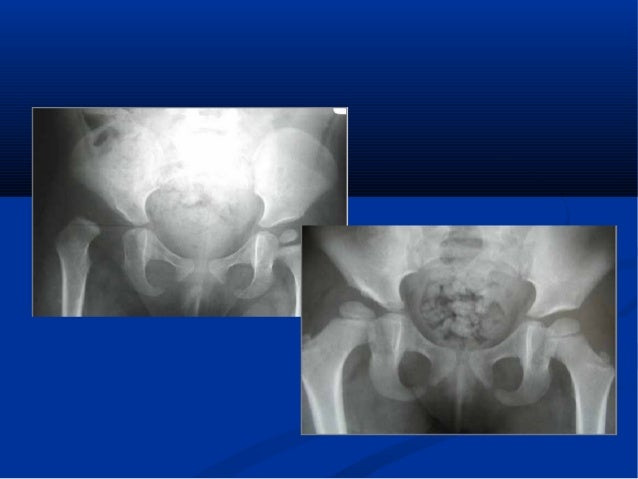

Luxation Congenitale De Hanche Chez L Enfant Sciencedirect

Descriptif de l'examen La luxation congénitale de la hanche (LCH) est une anomalie du développement de la hanche qui se manifeste par une instabilité, c'estàdire une mobilité anormale entre le bassin et le fémur La tête fémorale sort, ou peut sortir, en partie ou en totalité, de la cavité articulaire du bassin2 ABCdaire — Suivi collaboratif des 0 à 5 ans Emmaillotage serré Un autre facteur de risque est l'emmaillotage serré avec les membres inférieurs en extension et en adduction Il a été démontré qu'un emmaillotage sécuritaire (safe swadlling) diminue le risque de dysplasie de la hancheLa luxation congénitale de la hanche constitue une urgence orthopédique dont le dépistage précoce évite, pour certains nourrissons, un traitement chirurgical lourd et des séquelles importantes le CHU de Rennes affiche de très bons résultats en Ille et Vilaine qui ont permis la publication fin octobre d'un article de référence

Hanche#qui#se#manifeste#par#une#instabilité,#c'estàdire#une#mobilité#anormale#entre# le#bassin#etle#fémur#Latête#fémorale#sort,#ou#peutsor'r,#en#par'e#ou#en#totalité#de# lacavité#acétabulaire#(=cotyloïdienne),#alors#qu'une#hanche#normale#eststable# Elleconcerne# 6à/1000naissances en#France#avec#une#très##forte#prédominance#Hôpital Sud – BP – 353 Rennes cedex 2 Tél 02 99 26 71 87 email catherinetreguier@churennesfr La luxation congénitale de hanche (LCH) a fait l'objet en novembre 1991 d'une Conférence de Consensus organisée conjointement par la Société Française de Radiologie et le Groupe d'Étude en Orthopédie Pédiatrique 4Cabinet de radiologie en Illeetvilaine Trouvez tous les médecins proches de chez vous et prenez RDV pour une consultation Consultez les avis clients et les horaires en ligne pour prendre RDV chez un médecin de votre choix Retrouvez toutes les coordonnées et informations des professionnels dans l'annuaire PagesJaunes

√ radio hanche bébé paris Radio hanche bébé paris Pronostic Fonctionnel Engage Ppt Video Online Telecharger Radio hanche bébé paris Radio hanche bébé parisDysplasie De La Hanche Notre Envers Du Decor Maman De OuistitiHanche qui se manifeste par une instabilité de la hanche, c'estàdire une mobilité anormale entre le bassin et le fémur La tête fémorale sort, ou peut sortir, en partie ou en totalité de la cavité acétabulaire, alors qu'une hanche normale est stable (2)Patients et méthodes Étude prospective incluant les enfants consultant pour une boiterie non traumatique (n = 93) Ces enfants ont bénéficié d'un examen clinique, d'un bilan biologique et d'imagerie (radiographies du bassin (n = ), échographie de hanche initiale (n

Monsieur le Docteur Renémichel BARC Radiologue 12 pl Gambetta VANNES Conventionné (e) secteur 3 12 pl Gambetta VANNES Dimanche 07 Novembre Lundi 08 Novembre Mardi 09 NovembrePrix radio poumon 28,16€Echographie de hanche et luxation congénitale de hanche Généralités La luxation congénitale de la hanche (LCH) est une anomalie du développement de la hanche qui se manifeste par une instabilité, c'estàdire une mobilité anormale entre le bassin et le fémur